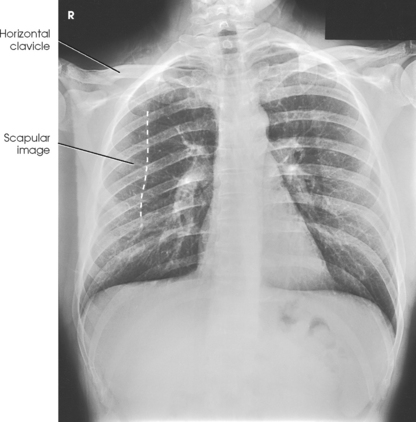

• Have the patient depress the shoulders and hold them in contact with the grid device to carry the clavicles below the lung apices. Except in the presence of an upper thoracic scoliosis, a faulty body position can be detected by the asymmetric appearance of the sternoclavicular joints. Compare the clavicular margins in Figs. 10-14 and 10-15.

• Rotate the shoulders forward so that both touch the vertical grid device. This movement will rotate the scapula outward and laterally to remove them from the lungs (Figs. 10-25 and 10-26).